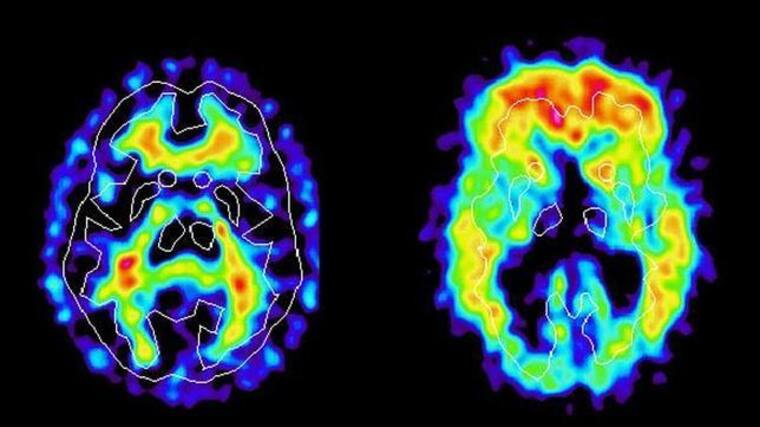

Esto notablemente podría afectar el funcionamiento del cerebro a largo plazo. La degeneración del tejido cerebral no está únicamente relacionada con el envejecimiento, sino también con factores ambientales y sociales, señala el portal ‘Psicología y Mente’.